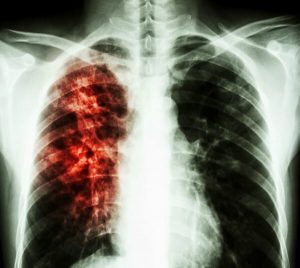

Активный туберкулёз — процесс, при котором у больных бактериологически обнаруживают М. tuberculosis или гистологически выявляют типичные для туберкулёза изменения (гранулёмы), а также характерные для туберкулёза клинико-рентгенологические признаки.

- Инфильтративный туберкулёз лёгких